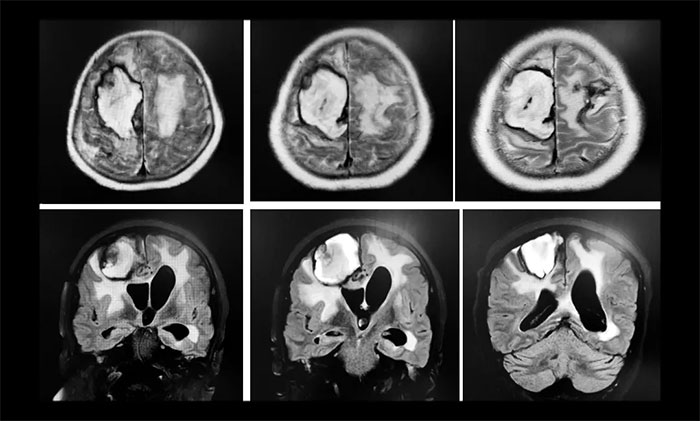

两次癫痫发作后,王阿姨陷入昏迷,再也没有醒来,并且生命体征不稳定,上了呼吸机,体温偏高,一直降不下来,医院给予相关对症治疗,但未有好转,如此一直持续了20天左右。直到7月11号,在做了CT后,医生发现脑占位,考虑肿瘤。“20天前,CT检查什么都没有,现在怎么会有肿瘤?”孙大叔提出质疑。之后行MRI示右侧额顶叶、基底节区及左侧额叶、左侧侧脑室出现大面积积血、脑水肿;MRV示右侧横窦、乙状窦、颈内静脉未见明确显示。医院影像科主任阅片后考虑静脉窦血栓。而此时距王阿姨发病已经过去了20天,错过了介入取栓时间窗,只能选择保守治疗。在住院治疗 42天后,王阿姨意识仍未恢复,还出现肺部感染,之后她辗转了多家医院。

▲ 入院时,行头颅MRI示:静脉窦血栓导致右侧额顶叶、基底节区及左侧额叶大面积出现脑积血、脑水肿